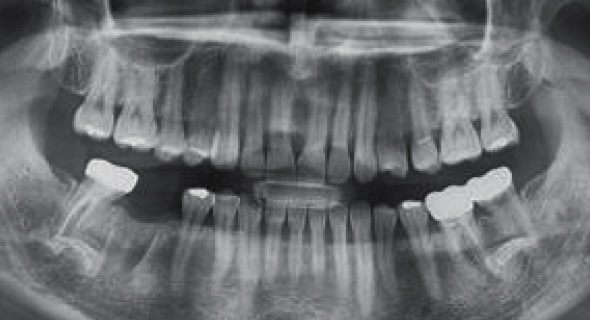

STEP 02

컴퓨터 가상 수술

- 컴퓨터 가상 수술로 식립 개수, 위치결정

- 가상 수술 계획대로 가이드 제작 -

02

컴퓨터로 미리 가상 수술하여

안전하고 오래가는 임플란트 수술이 됩니다. -

네비게이션 수술

컴퓨터 가상 수술을 통한 식립 위치 및 깊이 결정